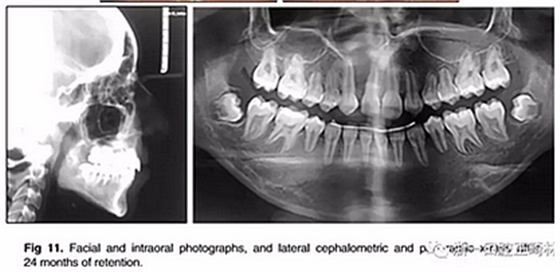

經(jīng)過24個月的保持后,咬合保持得很好(圖11 ; 圖12)。在上牙弓中,應(yīng)用固定舌側(cè)保持器以防止任何復(fù)發(fā)傾向。在下牙弓中,治療后拔除第三磨牙。

總體治療目標(biāo)已經(jīng)實現(xiàn)。病人的笑容和輪廓有所改善。咬合關(guān)系為I類磨牙關(guān)系,牙列整齊,牙尖交錯關(guān)系良好。反合和中線偏移得以矯正,并實現(xiàn)了正常的覆蓋和覆合。上下牙弓的擁擠問題完全解決,并且完成后全景片顯示良好的牙根傾斜度。疊加顯示良好的縱向和垂直控制(ANB,3.5°; SN / GoMe,42.5°)和矯正上下頜前牙傾斜度(1 / SN,96°; IMPA,87°)(圖10 ; 表)。